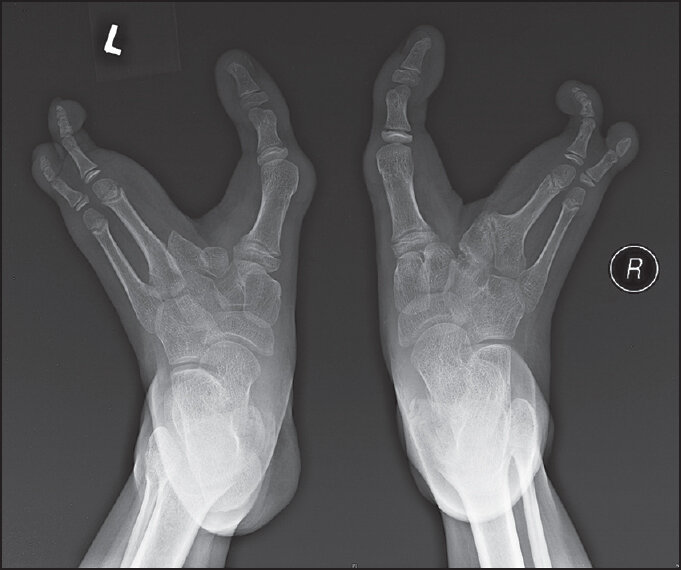

Эктродактилия - врождённое заболевание вызванное делецией, транслокацией и инверсией в 7-й хромосоме. Основной признак этого заболевания - клешнеобразные кисти руки или стопы. В среднем, заболевание встречается у 1 из 10 000 человек. Заболевание имеет больше косметологический дефект и люди, которые в итоге не проводят операцию по исправлению внешнего вида стопы\кисти, ведут вполне обычную жизнь. Но конечно, людям в современном обществе очень тяжело жить спокойной жизнью с такими дефектами, причём основная проблема носит именно психологический характер.